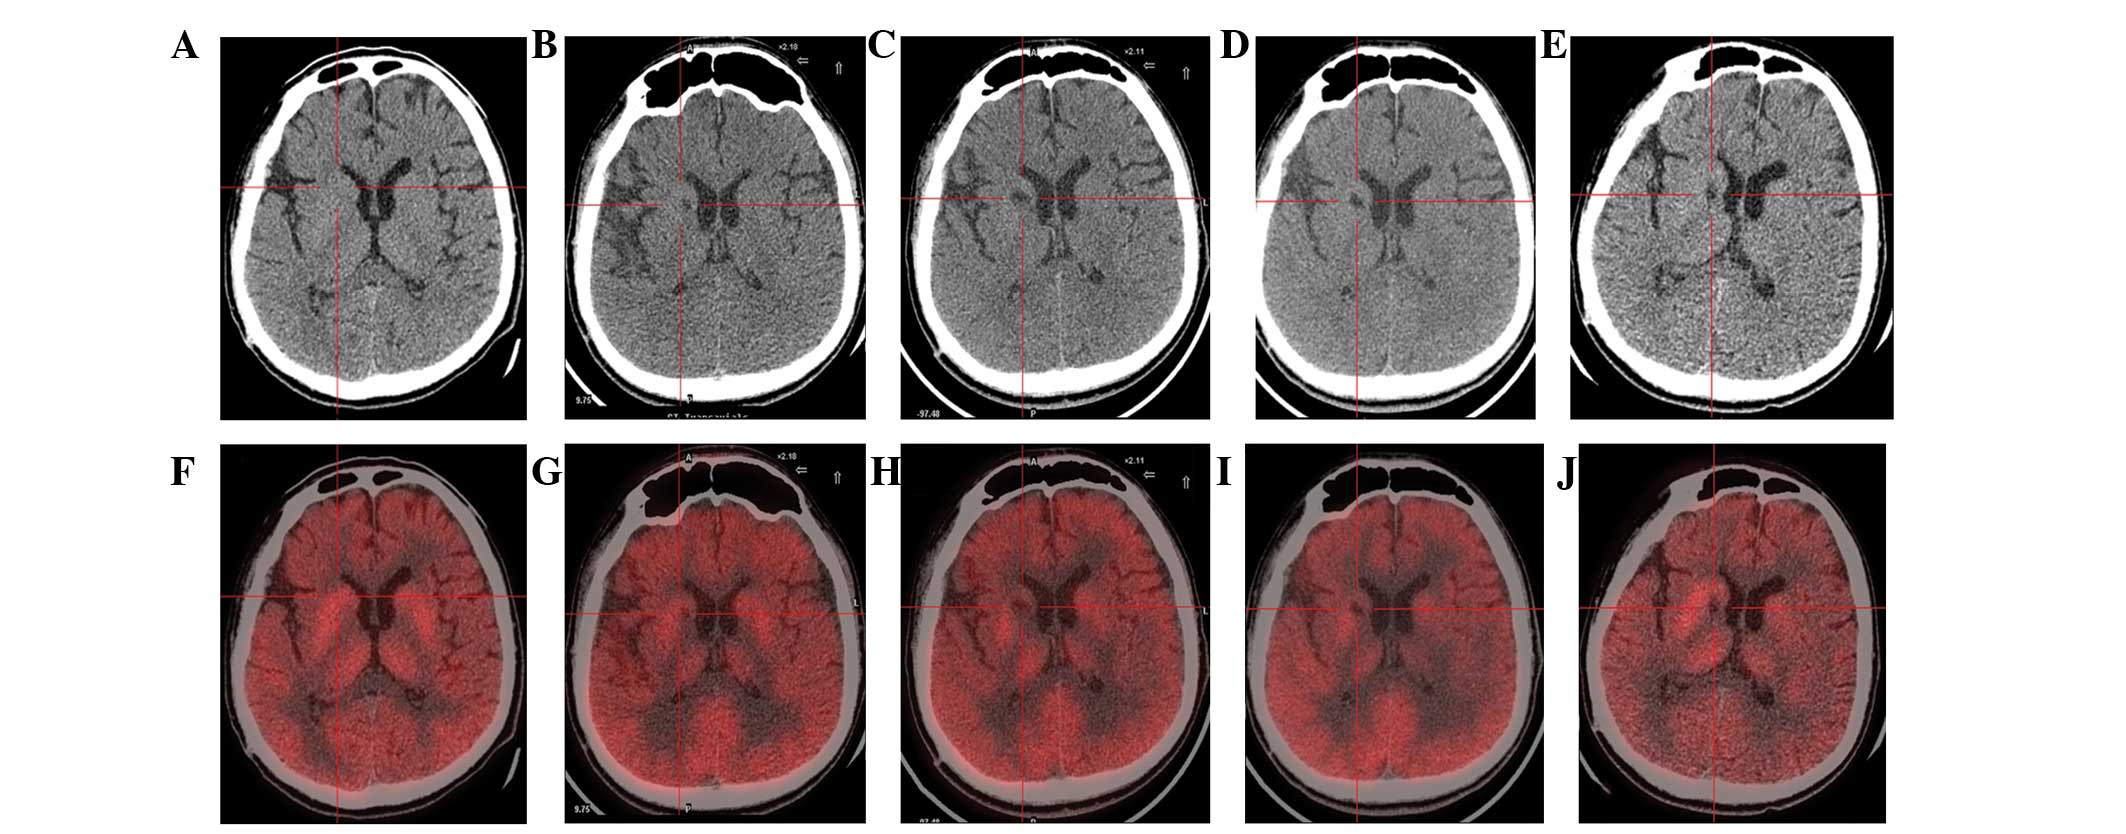

圖1:計算機斷層掃描 (CT) 和正電子發射斷層掃描 (PET) 掃描。

(A) 術前CT顯示腦萎縮。

(BE)術后1年、2年、3年、4年CT與術前相比均無明顯變化。

(F)術前18F-氟脫氧葡萄糖 (FDG) PET 掃描顯示,整個大腦皮層FDG攝取彌漫性減少,細胞核FDG攝取相對高于其他區域。術前1天,豆狀核和丘腦的標準化攝取值 (SUV) 平均值/最大值分別為4.3/5.8和3.3/4.5。

(GJ) 神經干細胞移植治療后分別 1、2、3 和 4 年的 18F-FDG PET 掃描顯示,雙側植入部位的豆狀核和丘腦對 18F-FDG的攝取增加(紅十字)與植入前相同部位進行比較。 豆狀核和丘腦的SUV*平均值/最大值在 1、2、分別是術后3年和4年。 該結果表明移植后葡萄糖代謝比移植前稍高。

CT(圖1b-e)和MRI(圖2b-d)掃描顯示4年隨訪期間沒有顯著變化。 手術前1天(圖1f)和手術后1、2、3和4年(圖1g-j) 獲得18F-FDGPET掃描。術后雙側植入部位豆狀核和丘腦18F-FDG攝取值較術前增加。這一結果表明,自移植以來,葡萄糖代謝逐年略有增加。